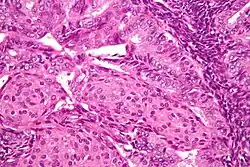

.jpg)

In endometrioid adenocarcinoma, the cancer cells grow in patterns reminiscent of normal endometrium, with many new glands formed from columnar epithelium with some abnormal nuclei. Low-grade endometrioid adenocarcinomas have well-differentiated cells, have not invaded the myometrium, and are seen alongside endometrial hyperplasia. The tumor's glands form very close together, without the stromal tissue that normally separates them. Higher-grade endometrioid adenocarcinomas have less well-differentiated cells, have more solid sheets of tumor cells no longer organized into glands, and are associated with an atrophied endometrium. There are several subtypes of endometrioid adenocarcinoma with similar prognoses, including villoglandular, secretory, and ciliated cell variants. There is also a subtype characterized by squamous differentiation. Some endometrioid adenocarcinomas have foci of mucinous carcinoma.[48]

The genetic mutations most commonly associated with endometrioid adenocarcinoma are in the genes PTEN, a tumor suppressor; PIK3CA, a kinase; KRAS, a GTPase that functions in signal transduction; and CTNNB1, involved in adhesion and cell signaling. The CTNNB1 (beta-catenin) gene is most commonly mutated in the squamous subtype of endometrioid adenocarcinoma.[49]